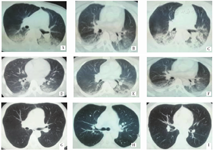

3例患者均为男性,平均年龄42岁,入院时均神志不清,呼之不应,1例伴全身抽搐。查体:双侧瞳孔凝视,对光反应迟钝。双肺听诊呼吸音粗,可闻及湿啰音。所有患者入院时脑电图、脑地形图均为界限或轻度异常,颅脑计算机断层扫描(CT)及核磁共振成像(MRI)均未见异常。事故发生后40 min内进行首次肺部CT检查结果示:双肺见对称性片状磨玻璃密度影,边缘模糊,考虑肺水肿可能。见图1。血气分析示:pH 7.1~7.3,氧分压(PO2)87.1~103.0 mmHg,二氧化碳分压(PCO2)34.7~42.4 mmHg;血常规示:白细胞计数(WBC)8.1×109~14.9×109/L;肺功能示:可疑小气道病变;痰培养示:肺炎克雷伯菌感染。以上结果均提示患者肺部损伤。

A:2018年5月5日患者1胸部CT;B:2018年5月5日患者2胸部CT;C:2018年5月5日患者3胸部CT;D:2018年5月6日患者1胸部CT;E:2018年5月6日患者2胸部CT);F:2018年5月6日患者3胸部CT;G:2018年5月11日患者1胸部CT;H:2018年5月11日患者2,胸部CT);I:2018年5月11日患者3胸部CT

3名患者入院后立即送ICU,行机械通气,同时给予甲泼尼龙静脉注射,并积极给予抗生素静脉点滴抗感染和保护重要脏器功能药物及高压氧治疗。治疗1 d后复查肺CT示:双肺斑片状、磨玻璃样影及双侧胸腔积液较前好转,病灶减少(图1D,图1E,图1F)。治疗2~3 d后复查肺CT示:磨玻璃影及胸腔积液较前进一步好转。治疗6 d后复查肺CT示:双肺CT未见明显异常(图1G,2H,3I)。ICU住院治疗7 d后,转神经内科病房。继续给予高压氧及脏器保护等对症支持治疗后,患者血气分析、血常规及痰培养结果均基本正常,患者分别于入院1月左右先后治疗好转出院。1月后随诊复查双肺CT提示正常。根据GBZ 31-2002《职业性急性硫化氢中毒诊断标准》[3]经青岛市职业病防治院专家组对3例患者均诊断为"职业性急性重度H2S中毒"。